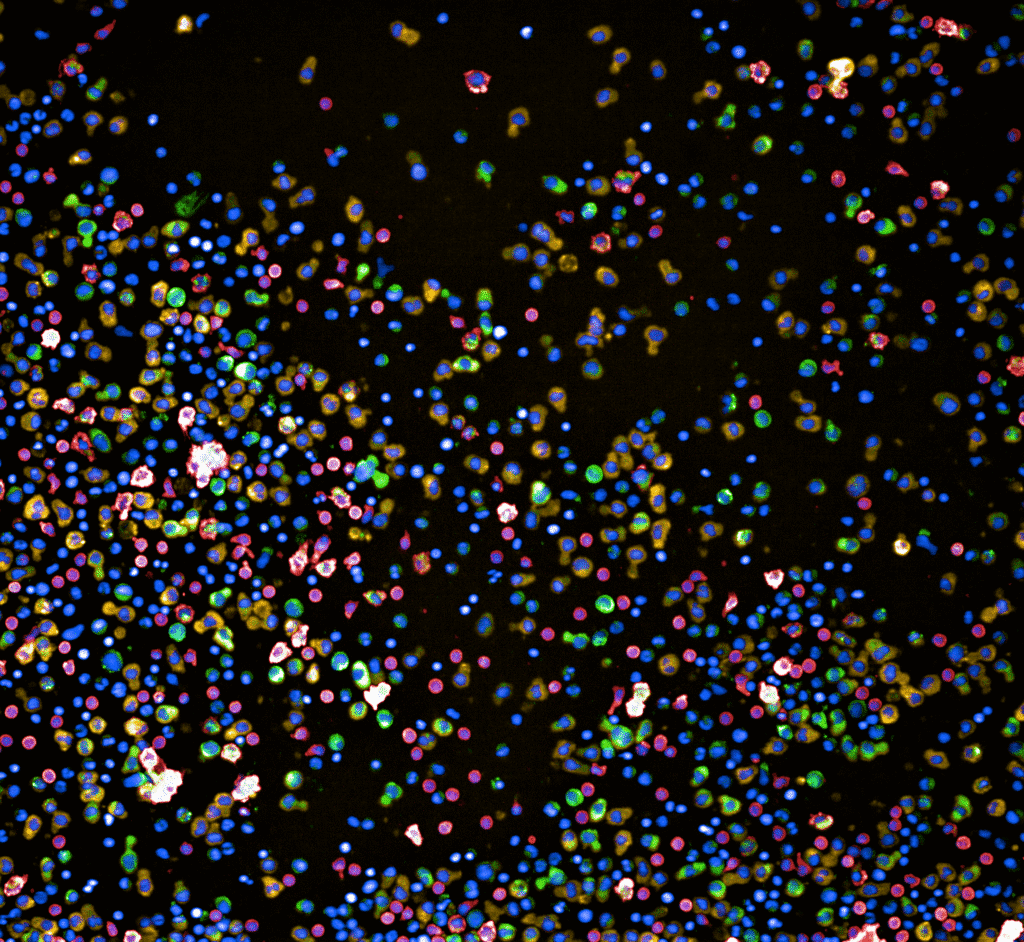

Die randomisierte, kontrollierte klinische Studie (Studienleiter: Prof. Dr. Alexandre Theocharides, MOH, USZ) untersucht, inwiefern die sogenannte Pharmakoskopie – eine am Labor von Prof. Berend Snijder (ETH Zürich) entwickelte, funktionelle Plattform für Präzisionsmedizin – zur Auswahl der individuell wirksamsten Therapie beitragen kann. Im Gegensatz zu rein genetischen Analysen analysiert die Pharmakoskopie die tatsächliche Wirkung zahlreicher Medikamente direkt an den Krebszellen der Patientinnen und Patienten – und erlaubt so eine Aussage zur zielgerichteten Behandlung.